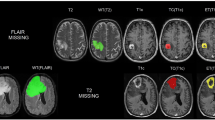

As shown in Fig. 5, the BraTS dataset contains three types of gliomas: peripheral edema (ED), non-enhancing tumor (NET), and enhancing tumor (ET). The task of the segmentation challenge is to accurately segment the three tumor regions: whole tumor (WT), tumor core (TC), and enhancing tumor (ET) using the information from the four modalities. The WT includes the ED, NET, and ET regions, while the TC includes the NET and ET regions. The BraTS 2018 dataset contains 285 patients in the training set and 66 cases in the validation set. The BraTS 2020 dataset contains 369 cases in the training set and 125 cases in the validation set, rendering it a more challenging set to process compared to BraTS 2018. The data for each patient contained T1, T1 CE, T2, and T2 FLAIR 4-contrast MRI images in addition to ground truth, whereas the validation set did not contain ground truth. All datasets were aligned, cranially stripped, and voxel-resampled to 1 × 1 × 1 mm³. The training set ground truth was drawn by experts.

The first and second columns show the brain MRI images of glioma patients with four different contrasts: T1, T1 CE, T2, and T2 FLAIR. The third column displays the corresponding 2D gold standards: the whole tumor region (WT, green + red + yellow), the tumor core region (TC, red + yellow), and the enhancing tumor region (ET, yellow).